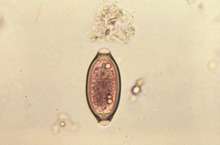

Diagnosis

For basic diagnosis, specific helminths can be generally identified from the faeces, and their eggs microscopically examined and enumerated using fecal egg count method. However, there are certain limitations such as the inability to identify mixed infections, and on clinical practice, the technique is inaccurate and unreliable.[11][12] A novel effective method for egg analysis is the Kato-Katz technique. It is a highly accurate and rapid method for A. lumbricoides and T. trichiura; however not so much for hookworm, which could be due to fast degeneration of the rather delicate hookworm eggs.[13]